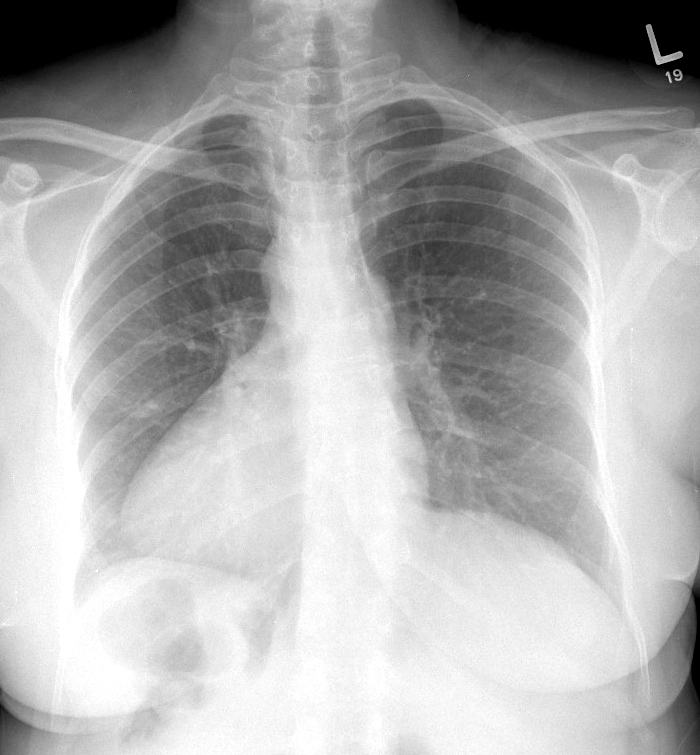

Gallery Congenital Situs Inversus

Situs Inversus